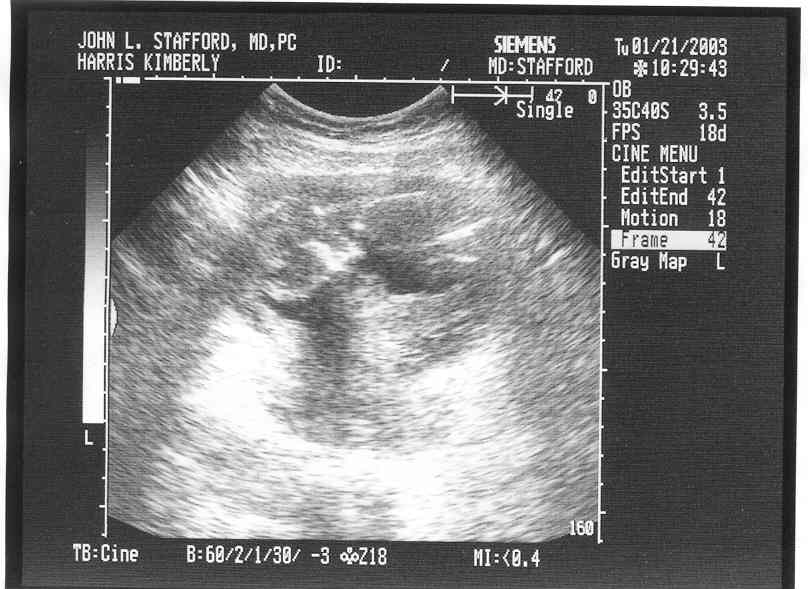

Ultrasound Pictures at 14 weeks, 2 days pregnant!

Here you can see his/her face and arm.